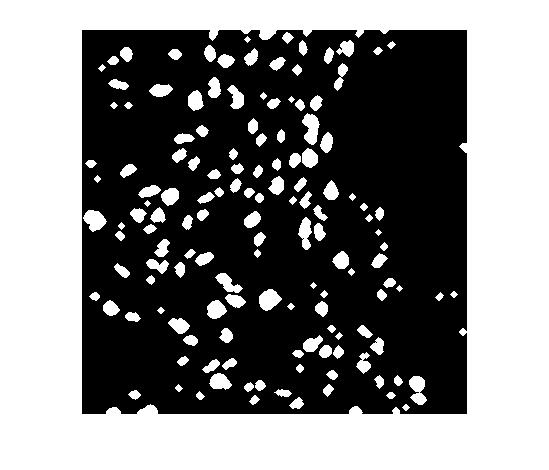

In this work, I propose a supervised deep learning-based model for accurate automatic cell nuclei segmentation. Given a tissue image, it begins with a deep convolutional neural network model to generate a probability map. Next, a threshold and morphological operations are applied to distinguish the background and the cells.

One of the significant benefits of the proposed method is that it can be applicable to different staining histopathology images taken of different patients. Due to the feature learning characteristic of deep convolutional neural network and the high level shape prior modeling, the proposed method is general enough to work properly across different image scenario like healthy, adenoma, hyperplasia.

Finally, I validated the proposed algorithm on several histopathology images using a range of different tissue from various patients with differents diseases.